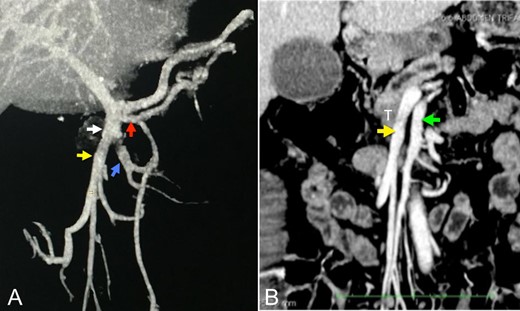

A 64-year-old white woman presenting cholestatic jaundice and weight loss. A solid lesion (3.5 × 2.2 cm2) in contact to the SMV posterior wall in the inferior border of the pancreas head was identified through multislice computed tomography. The 3D CT vascular reconstruction showed that SMV was formed by two ileal trunks, and that was a tumor in contact to one of them (Fig. 1). There was no tumor in contact with the superior mesentery artery. An upper digestive endoscopy and serum Ca 19-9 (2740 U/ml) were performed. The patient was submitted to preoperative enteral nutrition for 22 days. Tumor infiltration into the pancreatic head and into one of the SMV ileal tributaries was confirmed during surgery. The vascular clamp occlusion test showed immediate venous congestion in two-thirds of the distal small intestine (Fig. 2). No reconstruction attempt was performed, as well as the resection of the small intestine segment, due to the small size of the vessel and the reduced amount of viable residual intestine. A pancreatic-duodenal lymph node biopsy (frozen section examination: adenocarcinoma) and a biliodigestive anastomosis were carried out. In the postoperative period, the patient presented persistent vomiting, and a gastric bypass was performed. The patient was discharged 8 days later and referred for chemotherapy.

(A and B) Angiotomography showing the venous reconstructions of the portal-mesenteric axis and superior mesenteric artery in the coronal plane. White arrow: ileal trunk of the superior mesenteric vein. Red arrow: first jejunal branch (5.5 mm). Yellow arrow: venous tributary of the ileal venous ‘trunk’ involved by the tumor (9.6 mm). Blue arrow: venous tributary of the ileal trunk (9.3 mm). White arrow: ileal venous ‘trunk’. Green arrow: superior mesenteric artery (8 mm). T: tumor. It is important observing that, although the ileal venous ‘trunk’ involved by the tumor (yellow arrow) has the same diameter of the other ileal venous ‘trunks’ (blue arrow), a larger number of small tributary veins is observed in the first trunk.